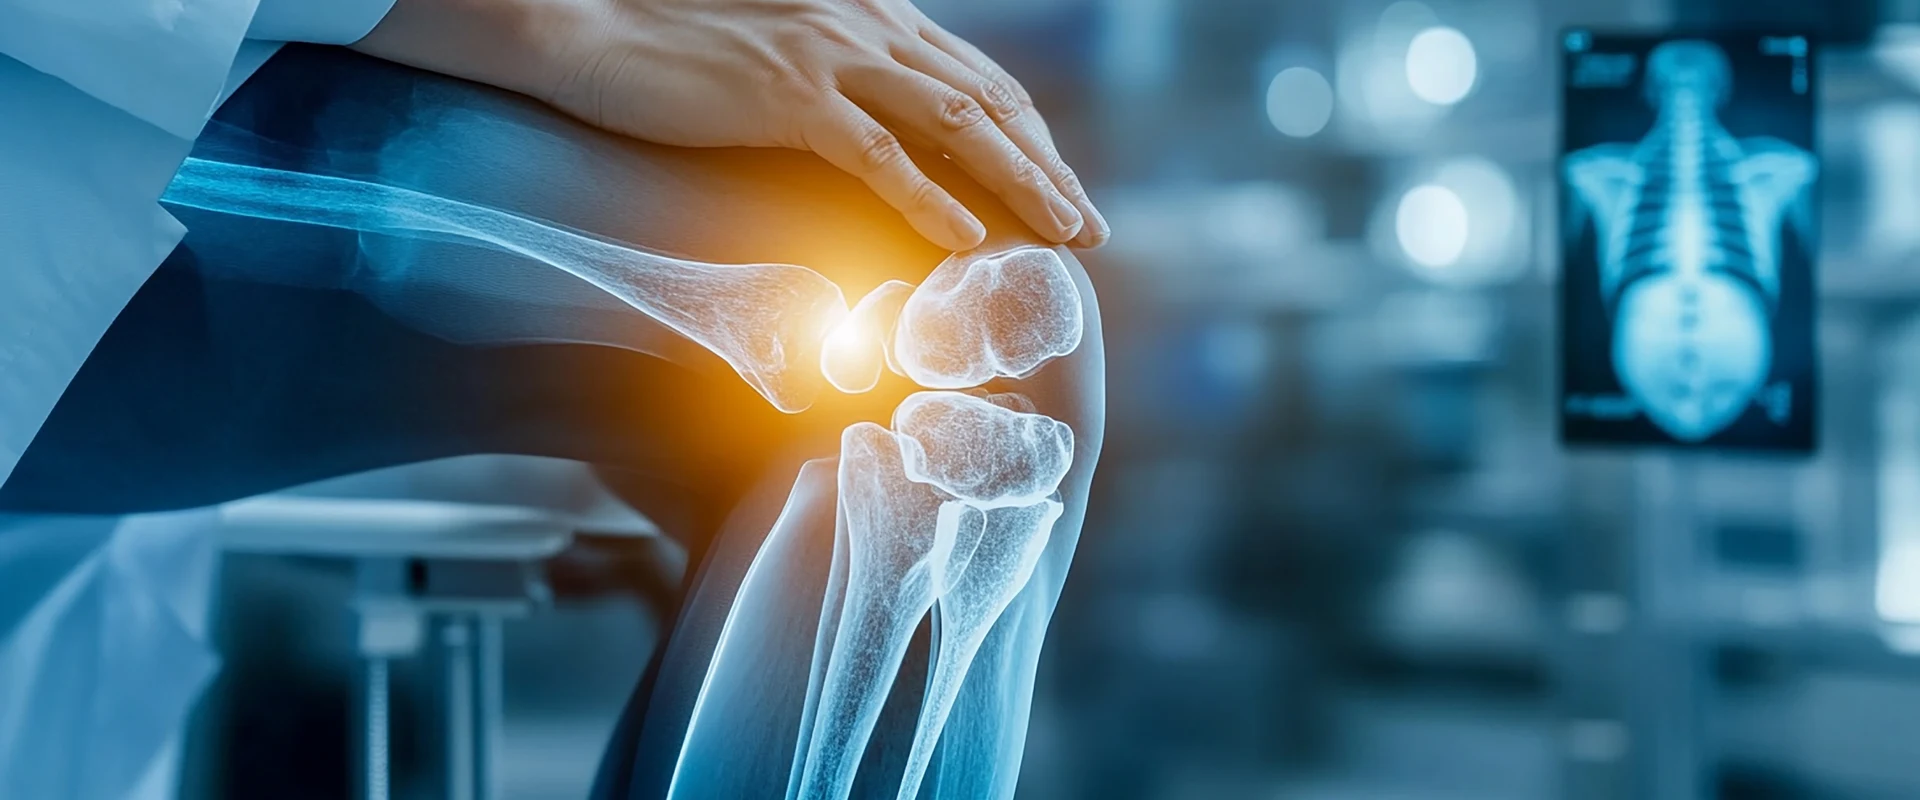

Orthopaedic

Department Of Orthopaedic, Joint Replacement & Sports Injury

The Department of Orthopaedics at Life Care Hospital specializes in the diagnosis and treatment of disorders affecting bones, joints, muscles, ligaments, and the spine. Our team of experienced orthopaedic surgeons, anesthetists, rehabilitation experts, and trained nursing staff work together to provide comprehensive and patient-focused care.

We offer a full range of orthopaedic services, from routine procedures to complex trauma management and joint replacement surgeries. With a strong focus on minimally invasive techniques, advanced surgical methods, and structured rehabilitation, we aim to reduce pain, restore mobility, and improve quality of life for our patients.

Common Orthopaedic Conditions Treated

- 1. Osteoarthritis : Degenerative joint disease causing pain, stiffness, and reduced movement.

- 6. Cartilage Damage : Degeneration or injury to joint cartilage causing pain and dysfunction.

- 7. Meniscal Tears : Damage to knee cartilage commonly seen in sports injuries.